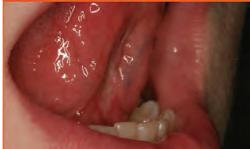

Unparalleled tissue management starts with rapid, profound hemostasis. For more than 40 years, dentists have trusted the immediate hemostatic power, detailed margins, and elimination of surface bleeding and sulcular fuid provided by Ultradent’s tissue management products.

Our complete line of solutions continuously sets the standard for superior control and predictability while offering dentists fast, reliable, and affordable products.

For continuous control of bleeding and sulcular fluid, no one offers a more complete line of solutions.

2. Give firm air/water spray to remove residual coagulum and to test for profound hemostasis. If bleeding continues, repeat.

3. After complete hemostasis has been attained, excellent retraction is achieved using Ultrapak™ knitted cord placed with the Ultrapak™ packer.

1. Well-healed tissue 2 weeks post-op.